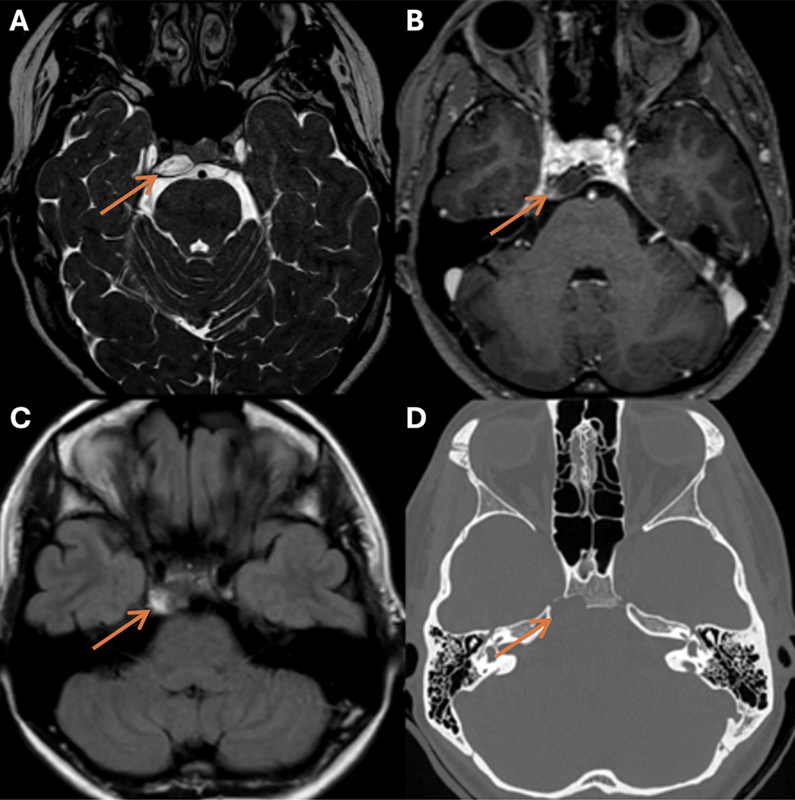

Case description: A 23-year-old woman presented with right abducens nerve palsy. Computed tomography and magnetic resonance imaging (MRI) revealed an off-midline petroclival lesion compressing the abducens nerve with characteristics of a chondrosarcoma. Preoperative MRI indicated spontaneous lesion regression, and the abducens nerve showed clinical improvement. Hence, the planned surgery was canceled. During the wait-and-scan period, abducens nerve palsy recurred. MRI confirmed lesion growth and showed an intratumoral linear structure indicative of blood. Even though preoperative MRI again demonstrated shrinkage, the lesion was surgically removed. Despite the unusual presentation, histopathological examination diagnosed a conventional chordoma. A second surgery was required to remove the residual tumor, after which the patient received high-dose photon beam therapy.